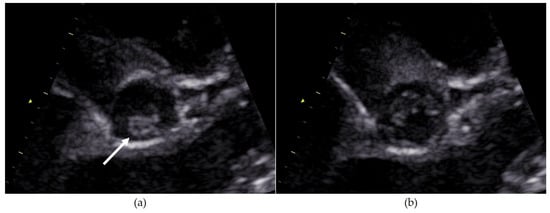

- In case 2, there was an air embolism in the left ventricle during the patient’s first catheterization. Due to depressed LV function with low contractility, the air bubble remained ventrally in the LV (Figure 8), where we managed to extract it with the catheter.